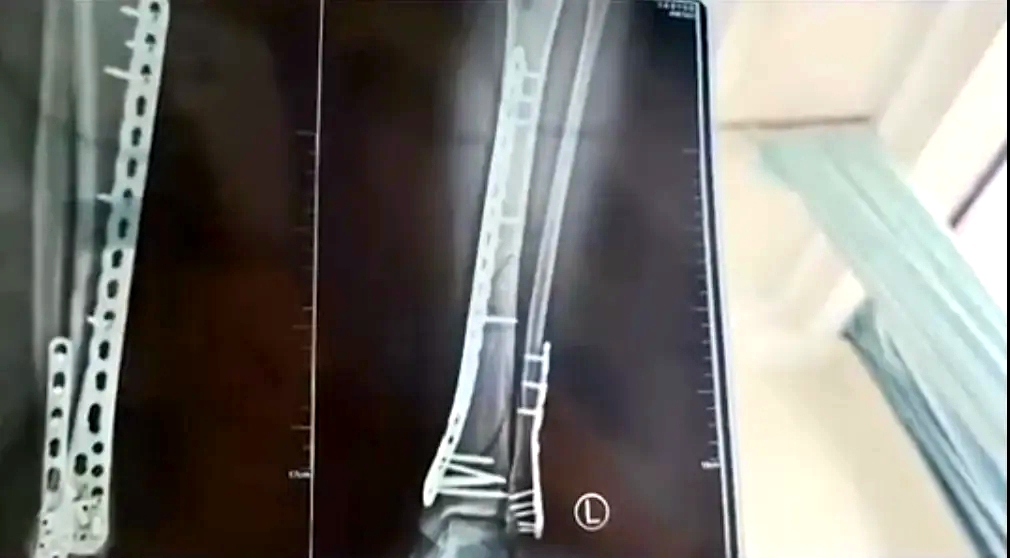

女子穿7cm厚洞洞鞋崴腳

致左腿粉碎性骨折

近日,甘肅蘭州的武女士稱母親節當天,自己穿7cm厚洞洞鞋下樓,不慎崴腳摔倒,致使左腿粉碎性骨折。

武女士稱:因為洞洞鞋的鞋底比較厚,腳掌中間又是凹進去的,自己下樓梯的時候,正好踩到凹進去的地方,當時腳沒有踩穩,整個人的重心往前撲,所有重力都集中在腿上,結果就骨折了。

該女子稱,目前已做完手術在家休養,不過下地得拄拐才行,且下地有時間限制,不能久站,而骨折完全康復可能需要3個月,她提醒大家穿增高鞋要注意。